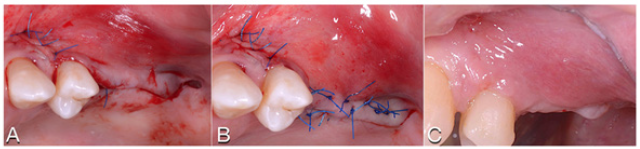

Figure 6: A. Sutures. B. Horizontal mattress sutures. C. Healing after 2 weeks.S

Figure 8: The new anatomy after 6 months.